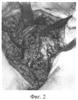

25.04.07 г. в СарНИИТО произведена операция: удаление пластины, замещение кортикального дефекта аутотрансплантатом (фиг.2), комбинированный чрескостный остеосинтез плеча (фиг.3) по предлагаемой методике. Рана зажила первичным натяжением. В послеоперационном периоде наблюдалось воспаление мягких тканей вокруг проксимального стержня, который был удален. После недельного консервативного лечения 16.08.07 г. ввели дополнительный стержень на этом же уровне. 23.10.07 г. демонтаж АВФ. После клинико-рентгенологического сращения (фиг.4) аппарат внешней фиксации 23.10.07 г. был демонтирован. Общий срок фиксации составил 6 месяцев.